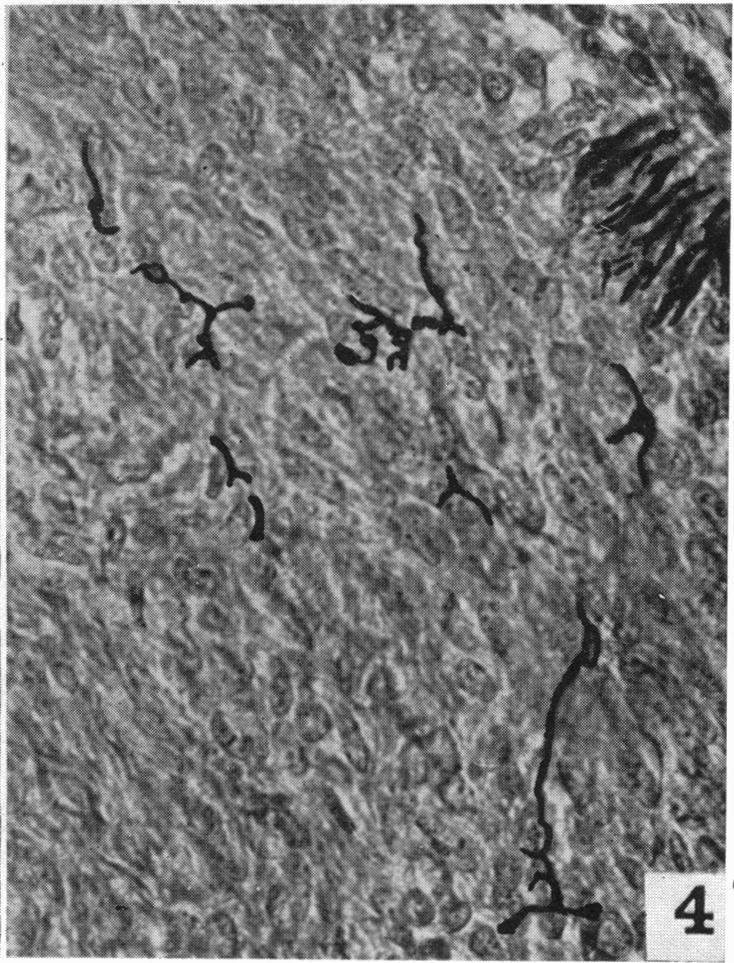

The nerve supply of the mammalian ductus arteriosus.

摘要